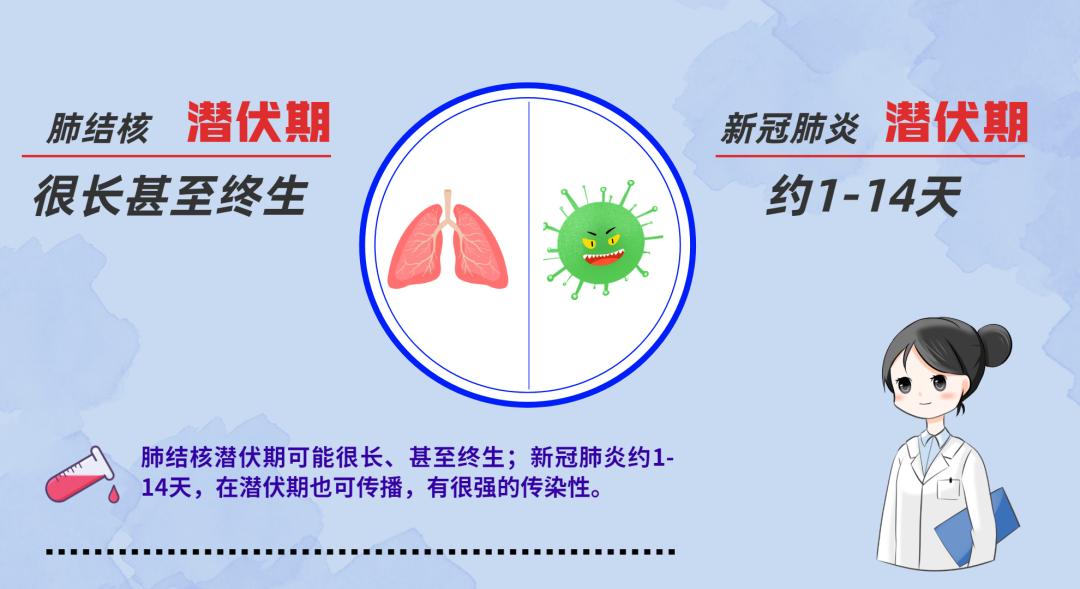

你太性急,几天就把人打倒,千军万马不灭你灭谁?哥教你一招,你看哥一进人的呼吸道先悄悄“潜伏”,谁抵抗力差,哥就出来在谁身上捣乱,所以几千年了,哈哈!他们还是干不掉我。你太嫩了!

等你被赶跑了,人们摘下口罩、有人还随地吐痰,我悄悄进入他们体内等待时机。哈哈!我们肺结核的家族就是这样兴旺!

要灭我,可没那么容易,治疗时间要6-8个月,有的人感觉不舒服还停药,那我就继续变身,穿上耐药盔甲与他们斗……一旦耐药,得治疗1年半到2年,还不一定能治好。有人说我们是“通过空气传播的癌症”,哈哈哈!

结核病是青年人容易发生的一种慢性和缓发的传染病。一年四季都可以发病,15岁到35岁的青少年是结核病的高发峰年龄。潜伏期4~8周。其中80%发生在肺部,其他部位(颈淋巴、脑膜、腹膜、肠、皮肤、骨骼)也可继发感染。人与人之间呼吸道传播是本病传染的主要方式。传染源是接触排菌的肺结核患者。随着环境污染和艾滋病的传播,结核病发病率越发强烈。除少数发病急促外,临床上多呈慢性过程。常有低热、乏力等全身症状和咳嗽、咯血等呼吸系统表现。

1.肺结核治疗全程为6-8个月,耐药肺结核治疗全程为18-24个月。

3.肺结核病人如果不规范治疗,容易产生耐药肺结核。病人一旦耐药,治愈率低,治疗费用高,社会危害大。